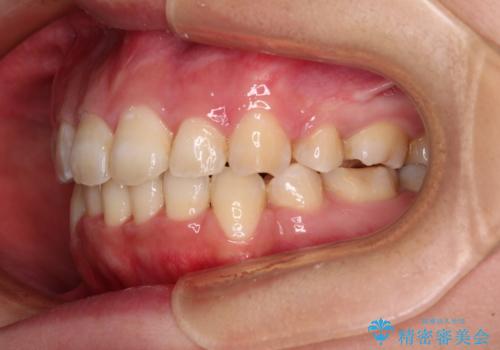

前歯の出っ歯と口の閉じにくさを抜歯矯正で改善 目立たないワイヤー矯正

- 上の前歯の出っ歯とでこぼこの歯並びを気にして来院された患者様です。

口元を積極的に引っ込めるために、上下左右の小臼歯4本を抜歯することとしました。

4本の歯を抜歯したことで、飛び出していた口元が引っ込み、横顔が大きく改善されました。

咬み合わせが悪化することのないようにスペースを閉じていくことができ、比較的スムーズに治療を進めることができました。